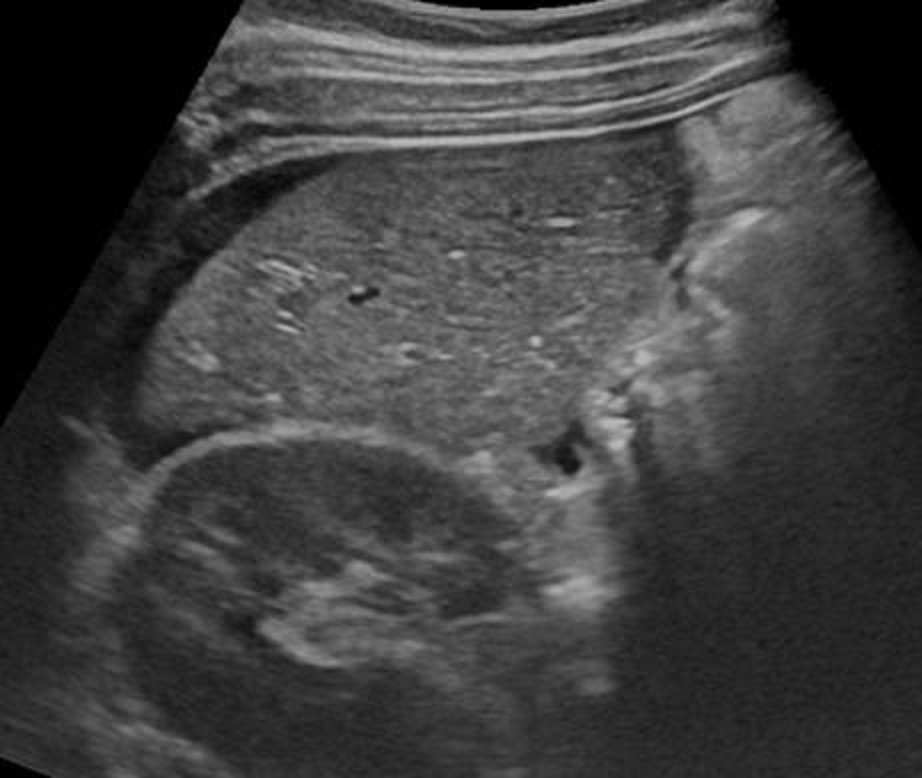

Dans les traumatismes de la

rate de grade grave de II - V , la signe indirecte

de traumatisme le plus souvent s'observe est image

de hemoperitoine peri-splenique ou globale

intra-peritoneale . Au dessus c'est image de

hemoperitoineale locale peripherique externe de la

rate , c'est une zone de hypoechogene a bien limite

peri-splenique . |

Image

echographique d'une traumatisme de la rate

compliquee avec une hemoperitoine localise

peripherique de la rate . On peut en s'observe de

zone hypoechogenecite a bien limite a inferieure et

a peri-splenique |